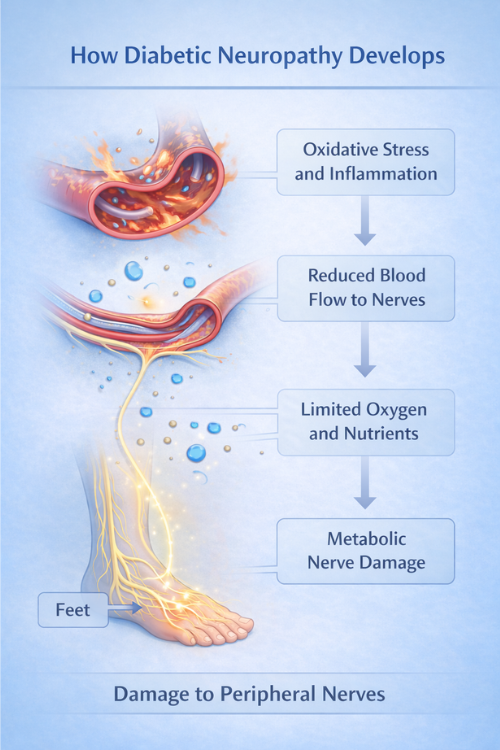

How Diabetic Neuropathy Develops

Diabetic neuropathy often develops gradually as metabolic changes influence nerve health. In many cases, long-term fluctuations in blood glucose may affect the small blood vessels that support nerve tissues.

As a result, nerves may receive less oxygen and fewer nutrients. Consequently, nerve signaling may gradually become less efficient over time.

Over time, repeated metabolic stress may influence how nerves communicate with muscles and sensory receptors. As a result, communication between nerve pathways and body tissues may gradually become less reliable. Because of these changes, signals between the brain and affected body areas may therefore become less reliable over time. Your Attractive Heading

Several biological factors may contribute to diabetic neuropathy. For instance, long-term metabolic stress may influence the small blood vessels that supply nutrients to nerve tissues. As a result, nerve cells may gradually receive less oxygen and fewer essential nutrients. Consequently, nerve signaling efficiency may slowly decline over time.

In addition, inflammation or oxidative stress may also affect the environment surrounding nerve fibers. Because of these influences, nerve signaling may gradually change. Consequently, communication between nerves and surrounding tissues may become less consistent.

Therefore, understanding the broader causes of nerve dysfunction may help explain how diabetic neuropathy develops over time.